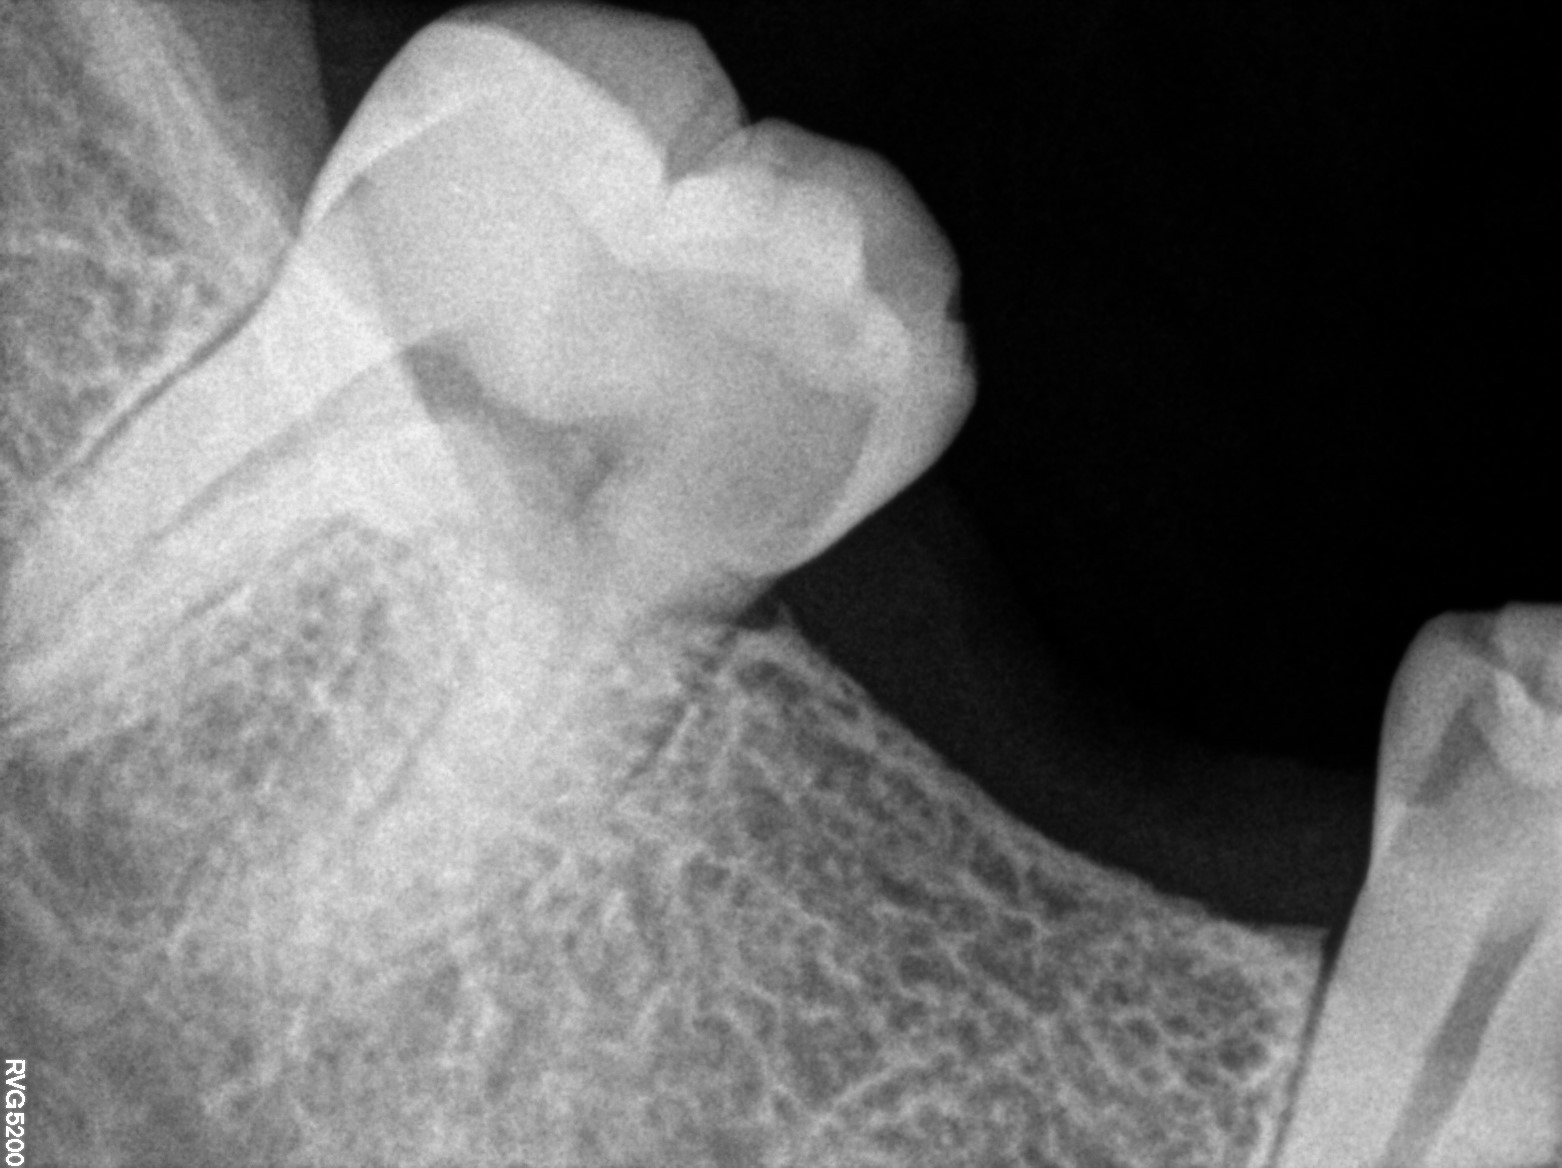

Dental Radiographs FHIR: DocumentReference · LOINC 24641-7

xray_1773248545_0.jpg

24641-7